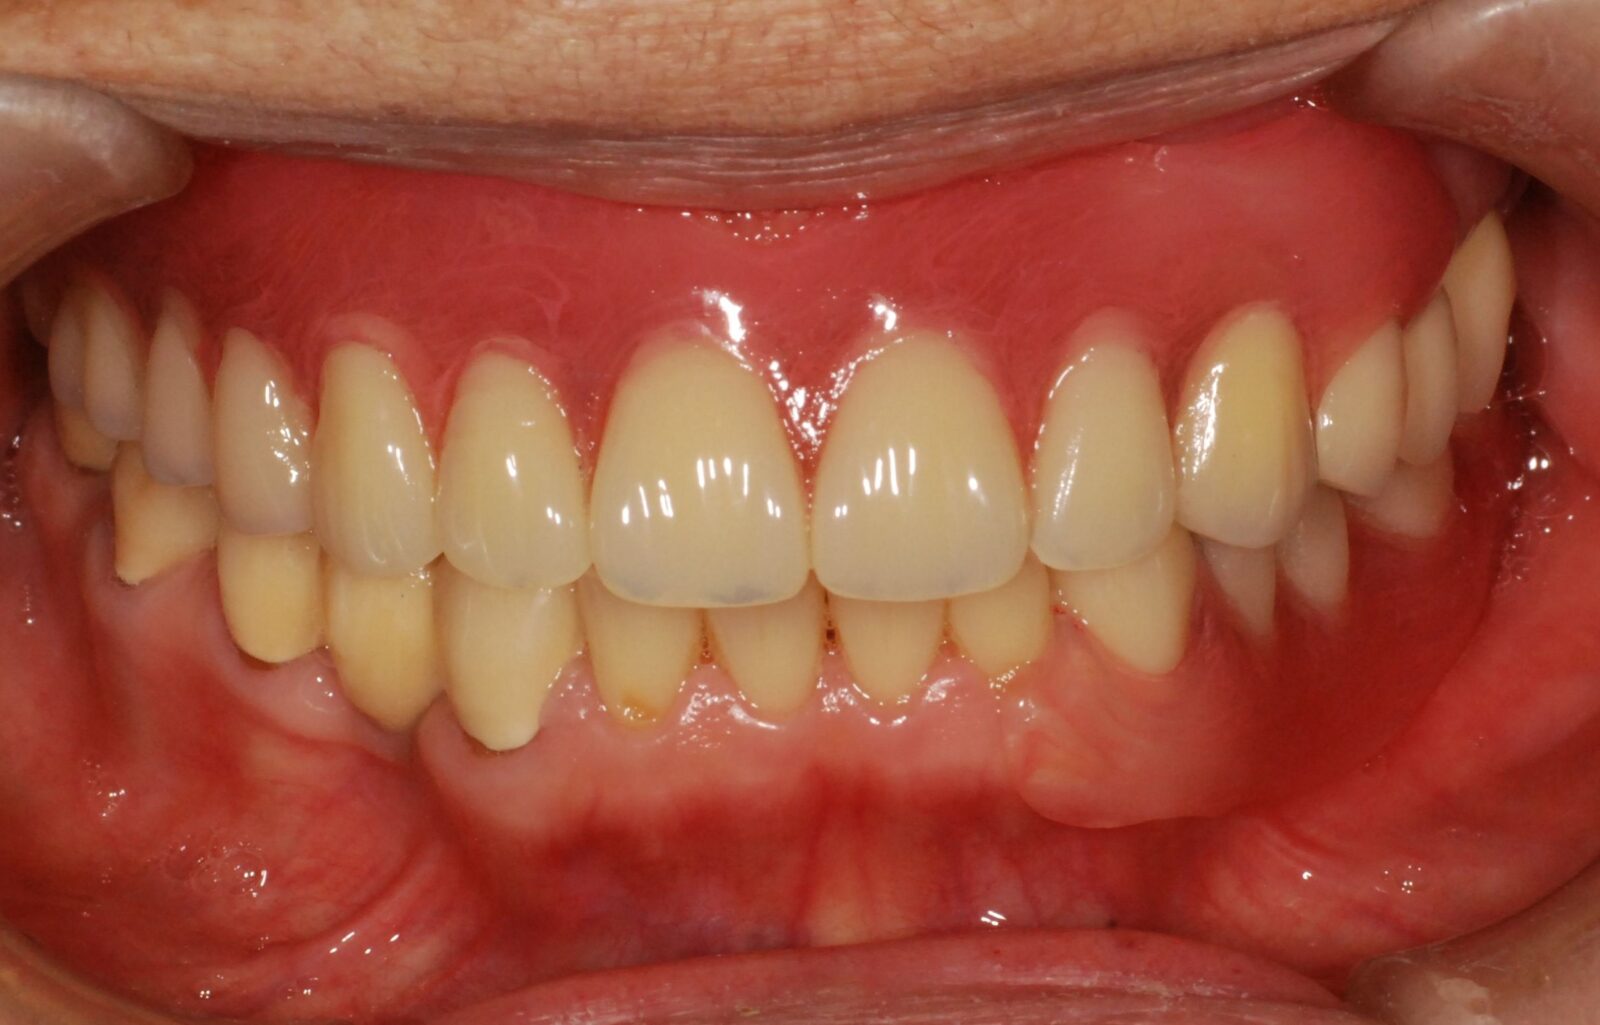

また、治療後の口元の状態が次の画像になります。

とても自然な口元になっています。